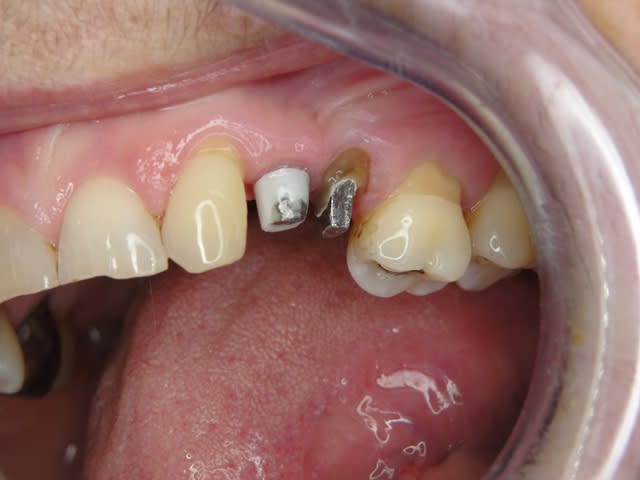

Bonjour flicflac je suis désolé de ma réponse tardive, oui il est vrai que ce n est pas beaucoup documenté ... je serai un menteur de dire que que je n ai jamais perdu des implants, surtout entre la 2eme et 8eme semaine après l implantation.Un échec vraiment à cause de la perte osseuse et avec le même process cela est arrivé une fois avec une madame, où l´os était encore infecté ( avant la chirurgie),mais après l ´échec (c était à la position 35) on a pu laisser le bridge. Malheureusement je n ai pas toutes les photos ici à Mallorque sur mon PC portable. Ci dessous une photo après 10 ans 46 47 et les implants au maxillaire.

Voilà une patiente que je revois à deux ans apres la pose d'un monobloc Classic line 3,5/12mm et prep cap zircone 12 degres 2/2 en 24.

La dent 25 était une couronne massive (dent à tenon type richmond) que j'ai taillé en inlay core.

Pour répondre à Céramik, oui la zircone se taille en bouche ( fraise Komet spécifique recommandées verte et blanche..mais tout diamant fait l'affaire). A la pose des céramo metalliques on observe la prep cap zircone au niveau du joint de

la couronne.

Radios 1,2,3 photo 1= jour de la pose de l'implant.

radio 4 photo 2 et 3= 8 semaines post pose de l'implant, ceramiques scéllées.

Radio 6, photo 4 et 5 controle à 24 mois.

Deux ans plus tard, la gencive a recouvert la zircone et on observe à la radio un gain osseux au niveau des micros spires.